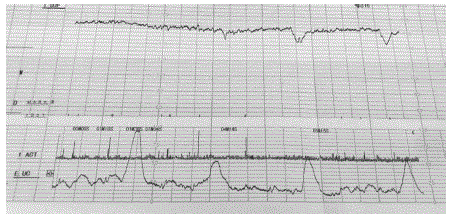

O partograma abaixo caracteriza:

Gestante, 32 anos de idade, secundigesta com uma cesárea anterior, 40 semanas e 2 dias de gravidez. Refere contrações irregulares e redução de movimentação fetal há 1 dia. Ao exame clínico, bom estado geral, corada, PA 120x70mmHg, altura uterina 30 cm, BCF presente rítmico. Toque vaginal com colo grosso, posterior, impérvio.

Vitalidade fetal: tônus adequado, movimentação corpórea e respiratória presentes, índice de líquido amniótico de 4,2 cm. Cardiotocografia apresentada.

Qual é a conduta adequada neste momento?